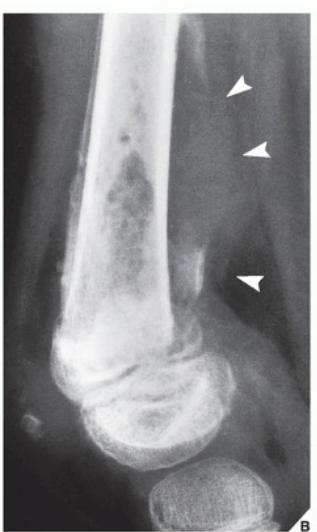

Osteosarcoma

Typical Presentation:

- Age: 10-20 years

- Pain and mass

- Location: Metaphysis of long bone

Characteristic Radiological Findings:

- Sunburst (Sunray) appearance

- Codmanโs triangle

- Periosteal reaction

- Bone eating appearance

Clinical Cases:

-

14-year-old patient with pain and swelling at lower right thigh

- Most important X-ray findings: Sun ray appearance, Codmanโs triangle

- Diagnosis: Osteosarcoma

14-year-old patient complaining of pain and swelling at lower R thigh

- Findings: Codmanโs triangle, Sun burst appearance